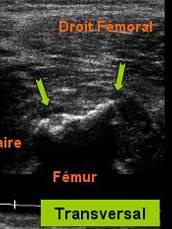

Echivalentul stadiului II al lui Rodineau se caracterizeaza prin

Fie o ingrosare focalizata, hiper ecogena,

centrala, sau a aponevrozie peri musculare

Fie de o dezorganizare mio-arhitecturala, care este inlocuita de

o zona cel mai frecvent hiper-ecogena

heterogena. Cautarea leziunilor mici este favorizata de miscari de contractie musculara

o zona cel mai frecvent

hiper-ecogena heterogena. Cautarea leziunilor mici este favorizata de miscari de contractie musculara